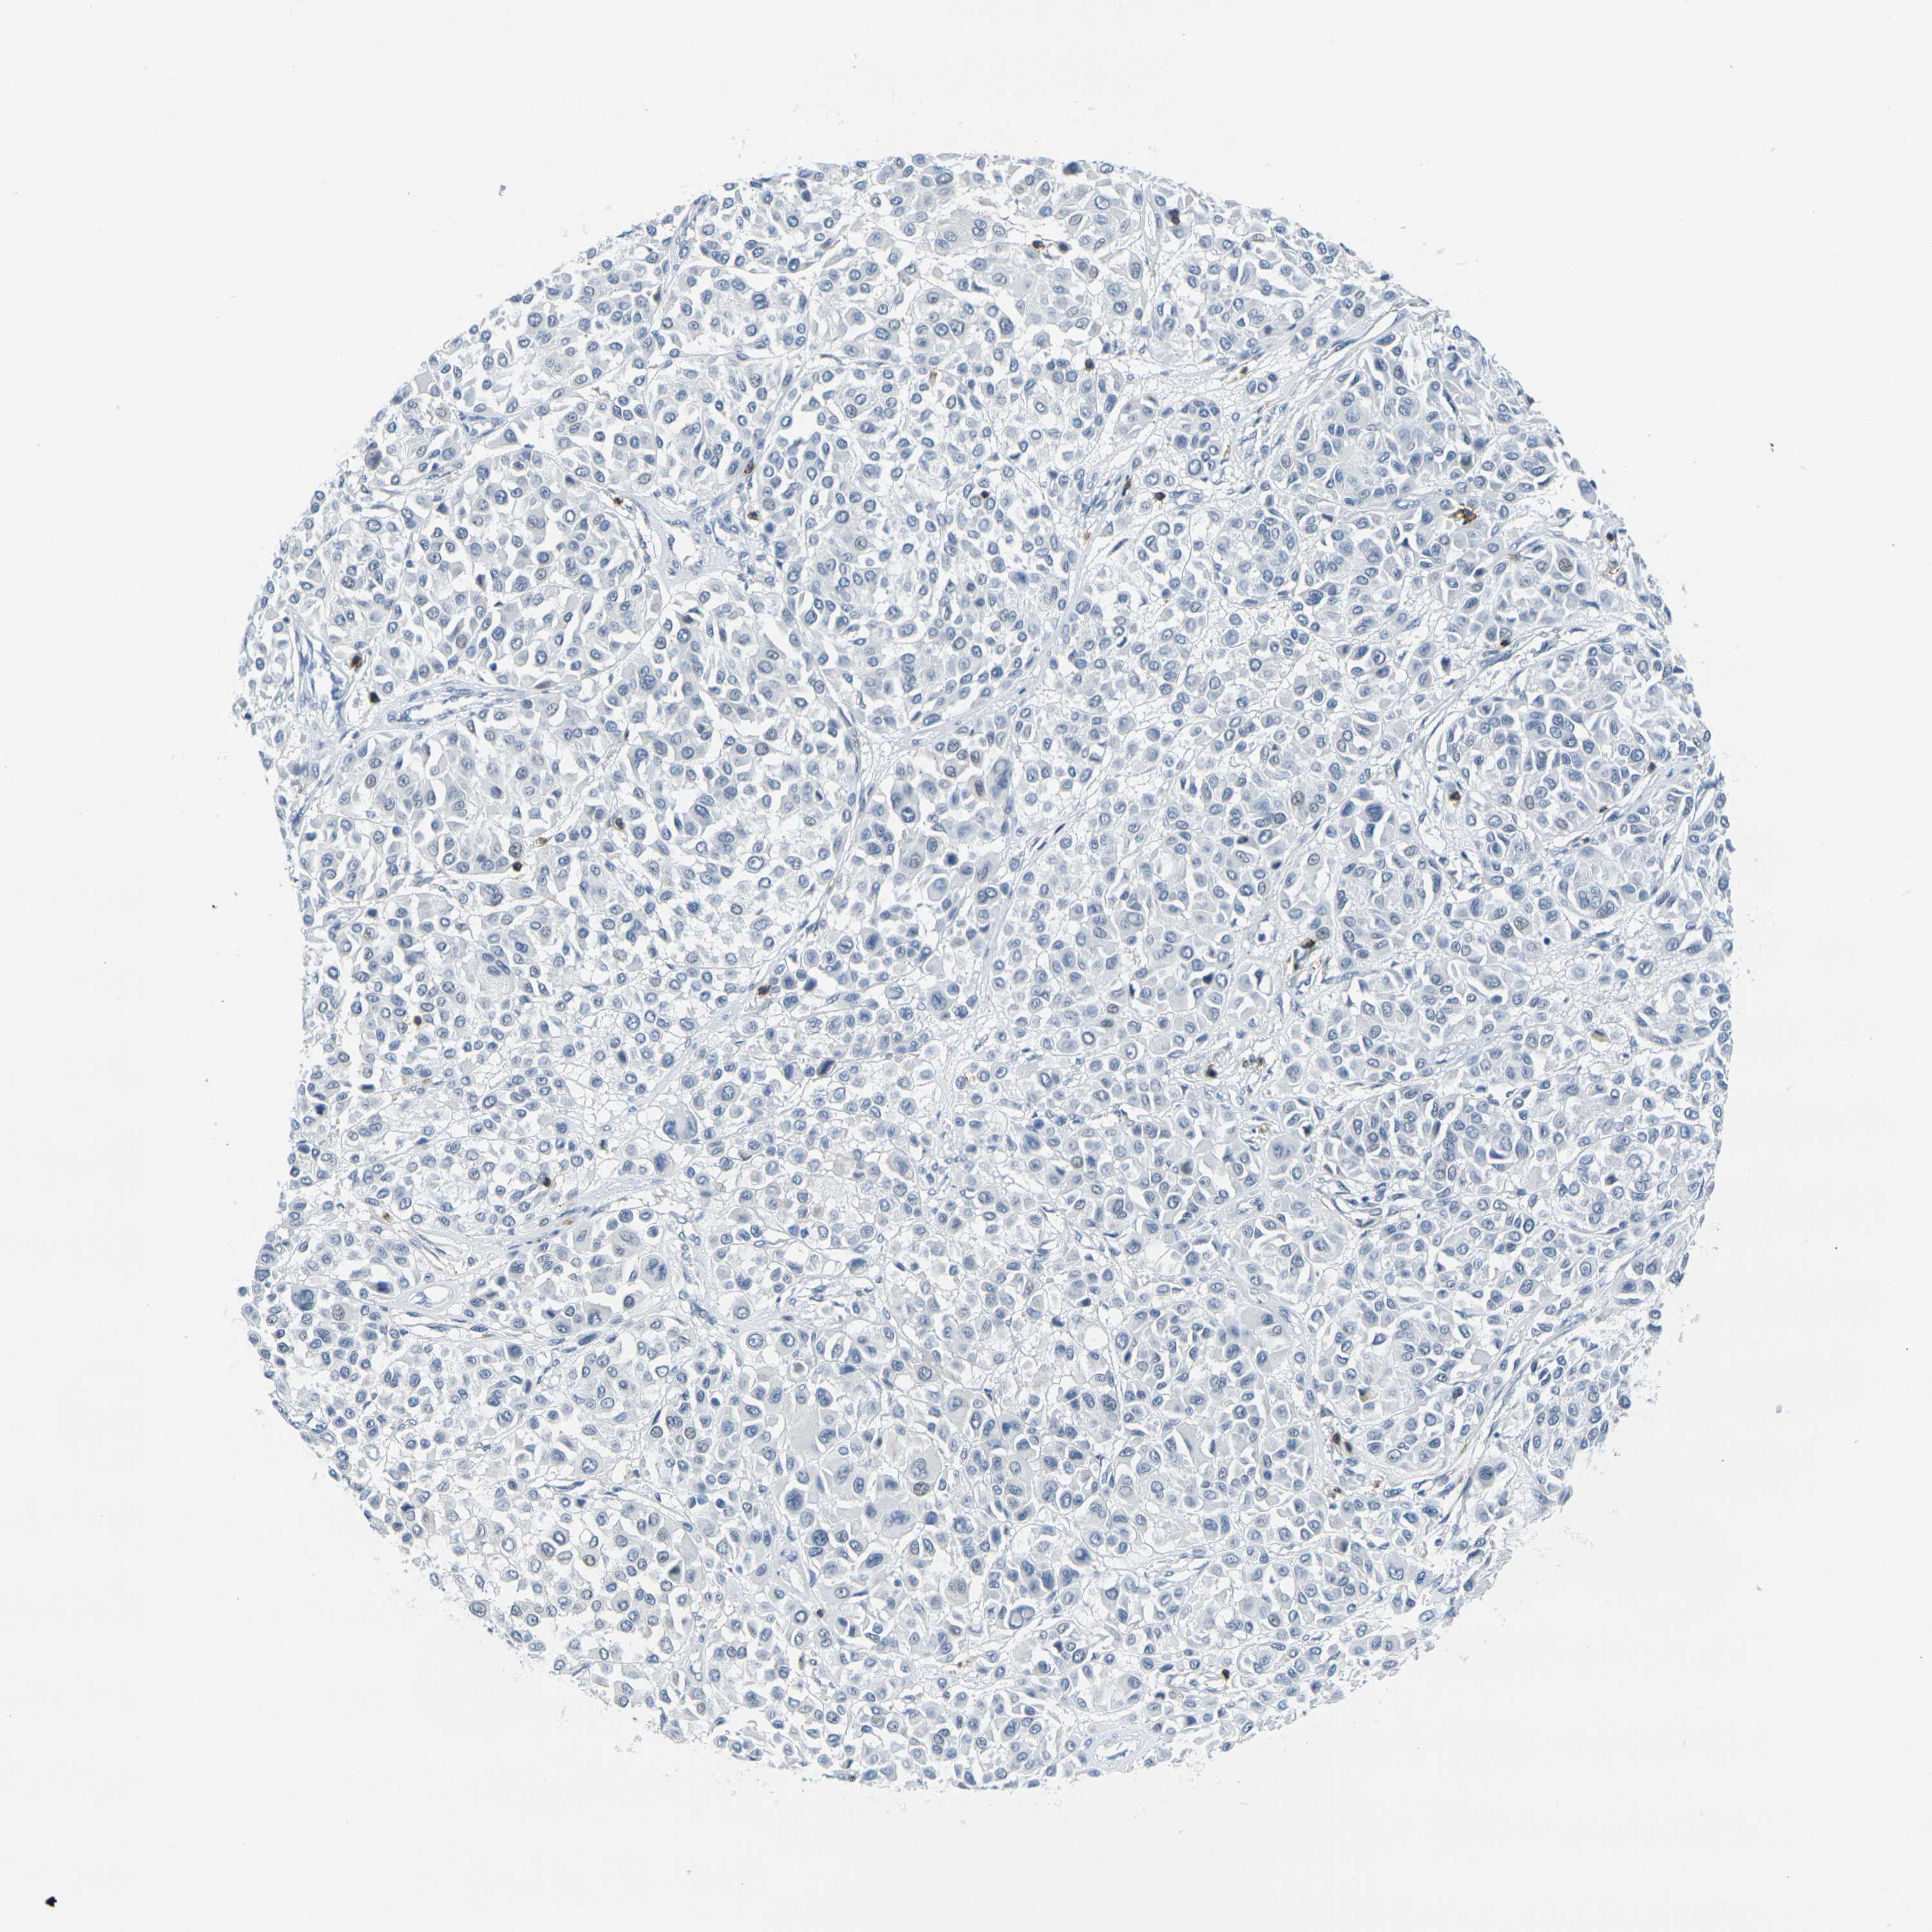

MELANOMA - Protein expressioni

A mouse-over function shows sample information and annotation data. Click on an image to view it in a full screen mode. Samples can be filtered based on level of antibody staining by selecting one or several of the following categories: high, medium, low and not detected. The assay and annotation is described here.

Note that samples used for immunohistochemistry by the Human Protein Atlas do not correspond to samples in the TCGA dataset.

Antibody stainingi

Antibody staining in the annotated cell types in the current human tissue is reported as not detected, low, medium, or high, based on conventional immunohistochemistry profiling in selected tissues. This score is based on the combination of the staining intensity and fraction of stained cells.

Each image is clickable and will lead to virtual microscopy that enables deeper exploration of all samples and also displays staining intensity scores, fraction scores and subcellular localization as well as patient and tissue information for each sample.

Antibody HPA071778

Antibody CAB013055

Malignant melanoma, NOS

Malignant melanoma, Metastatic site

Malignant melanoma in situ